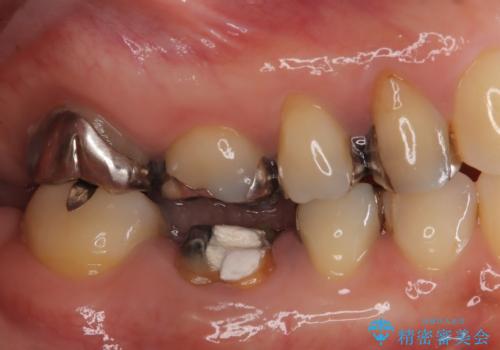

- 右下奥歯が虫歯で被せ物が取れてしまい、また噛めるようにしたいとのことで来院されました。

虫歯が大きく、歯を保存することが難しい状態でしたので、抜歯してインプラント治療を行うこととなりました。

骨の量は十分あったため、比較的短期間で治療は終了しました。

安定した咬み合わせとなり、痛みもなく安心して噛めるようになりました。